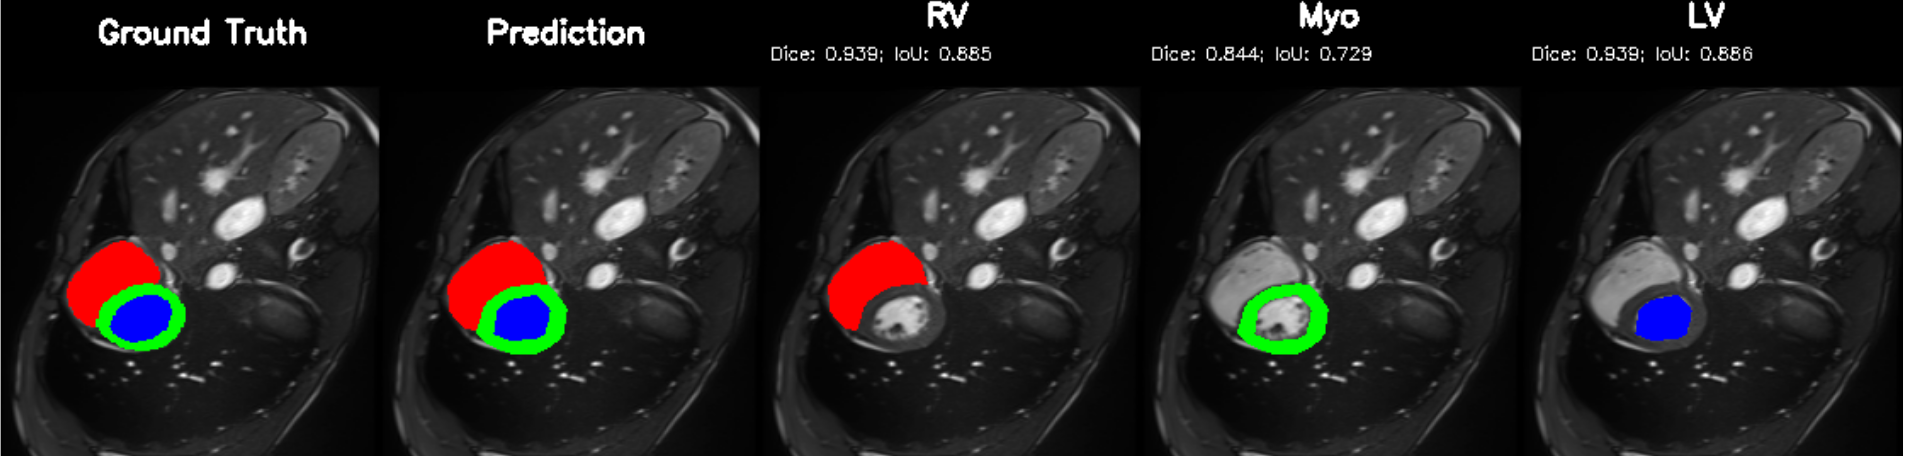

5.2 M&Ms Cine-MRI Generalization

Figure 8 illustrates segmentation outputs on the M&Ms (Multi-Centre, Multi-Vendor) cine-MRI dataset, which exhibits both contrast variation and vendor–specific acquisition differences compared to ACDC. The model retains consistent ventricular geometry, recovering LV and Myocardium structure without retraining, mirroring the zero-shot Dice performance of 74.8% (Table 11). Boundary thickness remains physiologically accurate, with only minor degradation in the right ventricle, an expected behaviour under cross-domain shifts and also reflected quantitatively in the ablation-driven robustness improvements from normalization and loss design. These results demonstrate that PULSE does not overfit to a single scanner distribution but instead transfers cardiac structure priors across unseen clinical environments.